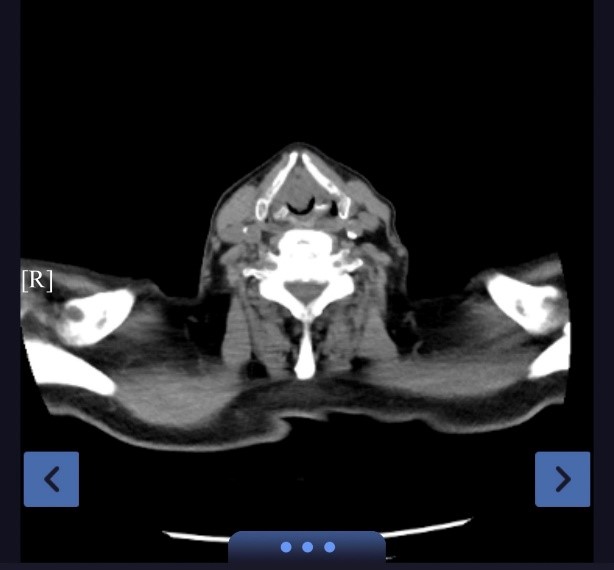

回溯病情,严老先生的求医之路充满波折。半年前,他无明显诱因出现声音嘶哑,在外院耳鼻喉科行喉镜检查未见异常,因而未引起足够重视。然而,病魔并未就此止步。1个月前,胸闷气急伴随着咳嗽咳痰症状悄然袭来,且在身体活动之后愈发严重。在外院接受住院抗感染治疗,病情却未得到有效控制。直至一周前,症状急剧恶化,夜间无法平卧,静息状态下不能耐受,短期体重下降15kg。患者及家属慕名来到苏大附四院蒋军红主任专家门诊,蒋主任凭借丰富的临床经验及精湛的医术,迅速判断出患者可能存在大气道狭窄,急诊完善颈胸CT证实了临床推断——巨大声门肿物伴大气道狭窄。